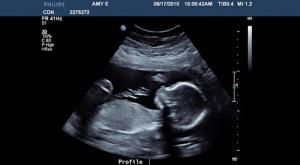

Quando os médicos do Hospital Rotunda, em Dublin, analisam o útero de Michelle uma última vez antes de fazer a raspagem, eles escutam o batimento cardíaco inconfundível de outro ser! Michelle está grávida, apesar de seu aborto. O que aconteceu foi que ela estava originalmente grávida de gêmeos, mas um deles não sobreviveu. O segundo bebê conseguiu ficar vivo, apesar dos médicos não saberem como isso foi possível!

Ninguém sabe se algum outro caso, semelhante a este, já aconteceu. Hoje com 18 meses, abebê está saudável e é o orgulho de seus pais e de seus irmãos, Ma (4) e Noah (2). Um outro mistério é que ninguém sabe como foi possível que Megan não tenha aparecido nos primeiros exames. Os médicos dizem que a menina ficou escondida no ultrassom, encoberta por sangue e outros fluidos residuais do aborto.